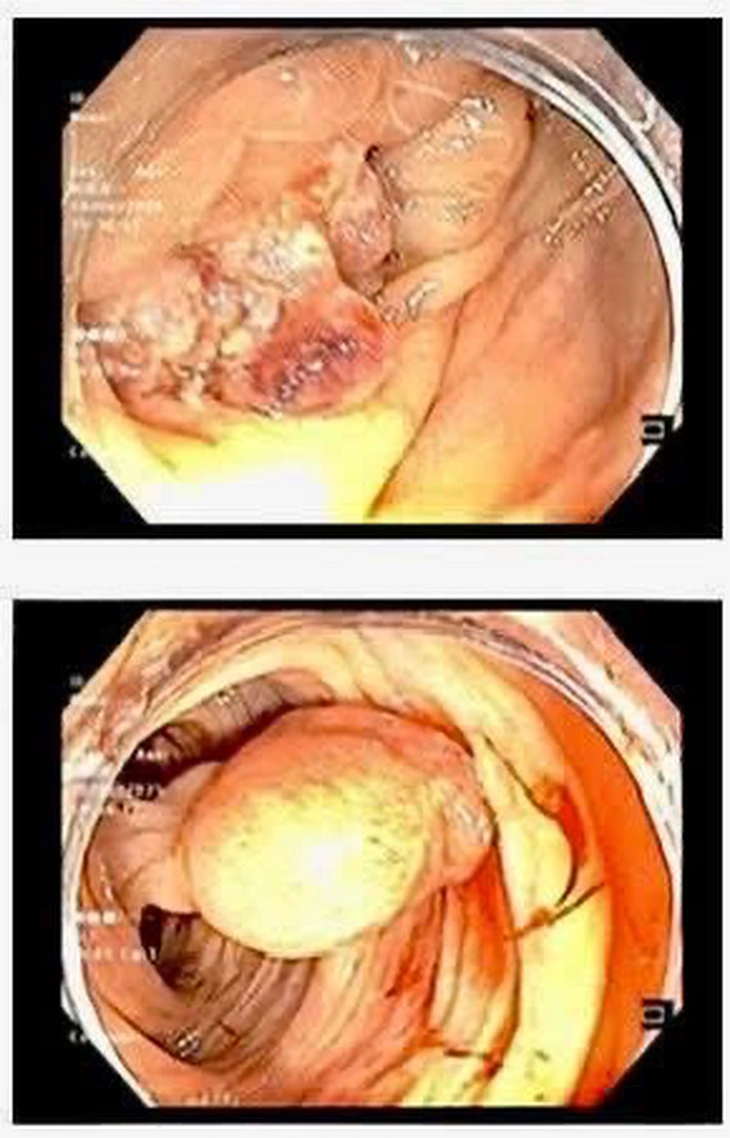

The patient is a 26-year-old male with a family history of colon cancer, with his father, aunt, uncle and cousin all having colon cancer. He was hospitalized due to prolonged abdominal pain and fatigue. Through examination and endoscopy, doctors discovered a large, ulcerated tumor in the transverse colon.

Pathology results showed that the patient had colon adenocarcinoma.

Image of large tumor detected by endoscopy - Photo: BVCC